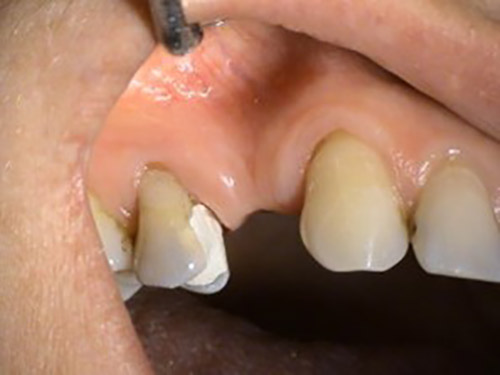

2. PHASE – state before making immediate impressions